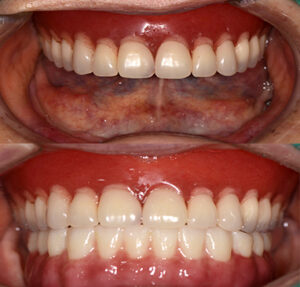

또한 완성된 보철물에서 치아와 잇몸을

동시에 제작하므로 퇴축된 잇몸의 보.상이 가능하여

입술 부분이 안으로 말려들어 가 있거나

길어 보이는 등의 부수적인 문제를

해결하는 부분에 도움을 주어

자연스러운 완성이 가능해요.

완료 후의 모습을 보시면 구강에 맞는 형태와

모양으로 임플란트가 완성된 모습을 볼 수 있는데요.

보철물까지 완료된 후의 사진이에요.

.

위에 사용하시던 틀니와 교합이 알맞게

맞물리는 것을 볼 수 있는데요.

심미적으로도 만.족하시고 틀니처럼

탈락하지 않아 좋아하셨어요.